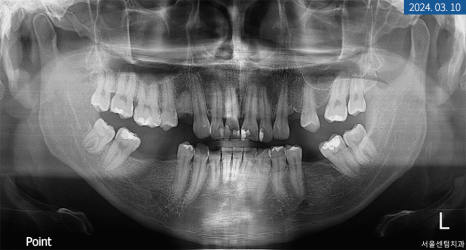

이번에 찾아오신 20대 환자분의 상태를 정확히 파악하기 위해 파노라마 엑스레이 촬영을 해보니 위턱과 아래턱 영구치 상실이 여러 군데 보였고 상악 전치부 부분 크랙이 심했습니다. 연령이 낮아 큰 골 소실은 없었지만 우측 상악 제1 소구치는 하방에 염증이 생겨 픽스처를 심는다면 GBR이 필요했는데요.

크랙도 범주가 크고 깊어 그대로 놔두게 되면 치수 감염과 하방 파절이 우려되어 조속한 대처가 필요했습니다.

아래턱도 자연치가 상실된 곳이 있었지만 먼저 위턱 개선을 원하셔서 요구 사항에 맞춰 계획을 세워드렸습니다.

진단

상실된 #14번은 합성골을 이식한 후 네이바이오텍 픽스처 직경 4.5mm, 높이 10mm로 이식하기로 했고 당일 좌측 상악 #15번 소구치도 동일한 브래드의 픽스처 4.0mm x 8.5mm 크기로 심기로 했습니다. 크랙이 심한 앞니와 측절치는 보철물을 수복해서 영구치를 보존하기로 했으며 크라운보다 치아 삭제량이 적고 심미적인 라미네이트를 부착하기로 했습니다.